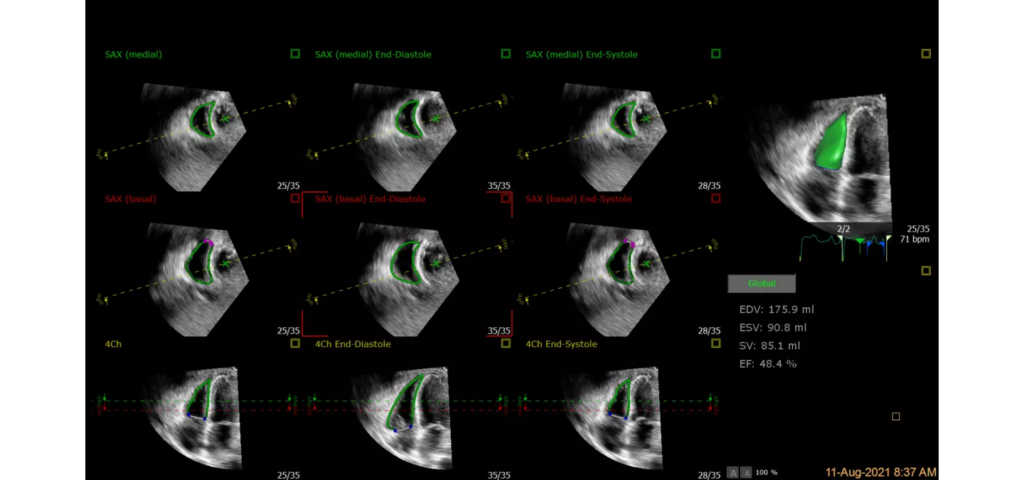

EPIQ CVx, our premium cardiovascular ultrasound system built on our innovative, modular, industry-leading ultrasound platform, has powerful AI-based capabilities and advanced diagnostic solutions to help you transcend today’s complexities and propel echocardiography into the next dimension. This enables you to achieve greater consistency, accessible innovation, smarter workflows, and easier scalability.